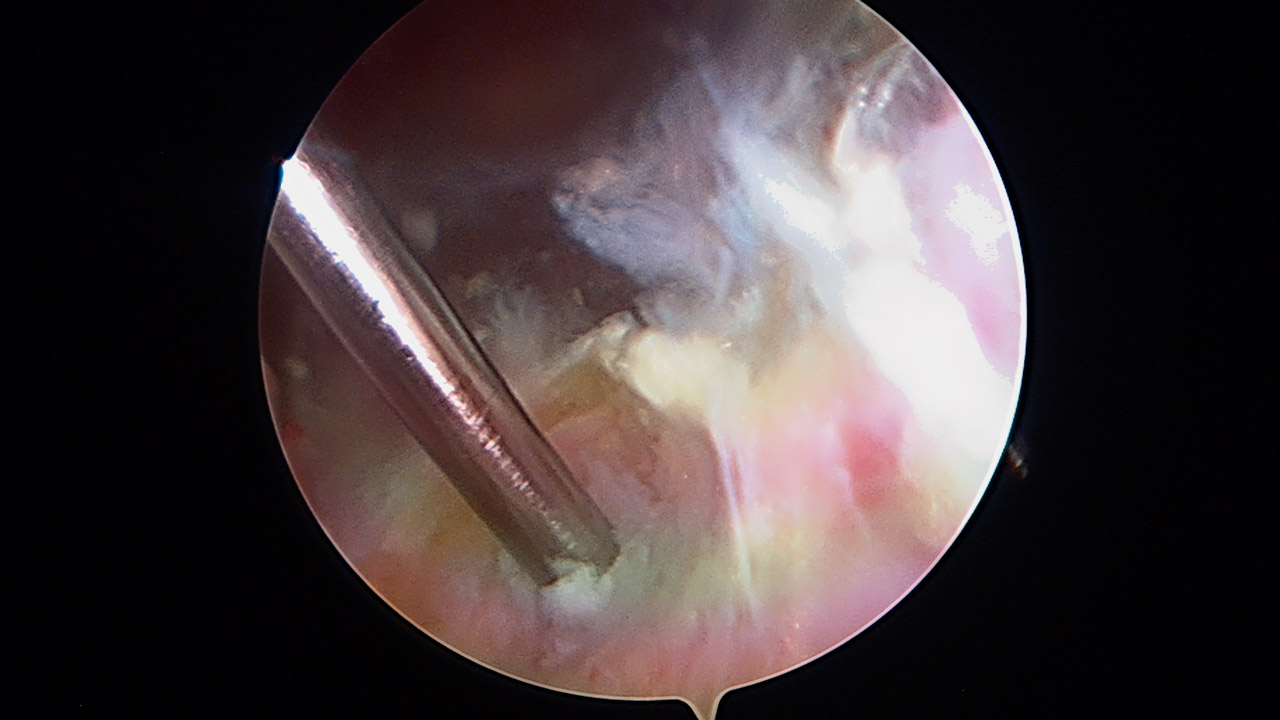

Presentamos una técnica quirúrgica artroscópica para los casos de inestabilidad traumática o atraumática de hombro, con hiperlaxitud multidireccional asociada, en los que hayan fracasado los tratamientos conservadores u otras técnicas quirúrgicas de plicatura capsular, y no presenten déficit óseo importante. Consiste en la plicatura del ligamento glenohumeral inferior (anteroinferior y posteroinferior) y la realización de una ligamentoplastia de refuerzo anterior artroscópica con aloinjerto en disposición transubescapular.

We present an arthroscopic surgical technique for cases of traumatic instability or atraumatic of the shoulder, with associated multidirectional hyperlaxity in which conservative treatments have failed, or other surgical techniques of plication capsular, and do not present major bone deficits. It consists of the plication of the lower glenohumeral ligament (anteroinferior and posteroinferior) and the accomplishment of an arthroscopic anterior reinforcement ligamentoplasty with allograft in a trans-scapular arrangement.